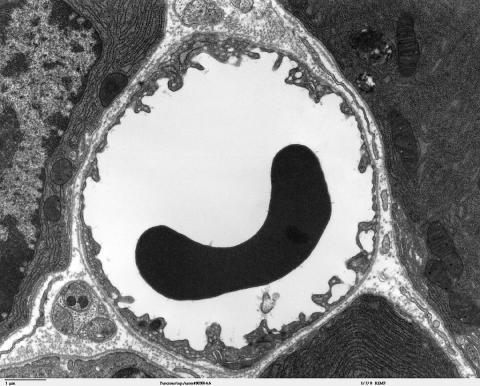

1024px-A_red_blood_cell_in_a_capillary_pancreatic_tissue_-_TEM.jpg

과학자들이 첨단 장비를 적용해 그동안 5~10 미크론 직경의 모세혈관 내 혈류 활동을 밝혀내기 시작했다. 불치병 조기 진단에 사용될 것으로 예상돼 의료계의 관심이 집중되고 있다. ⓒWikipedia

모세혈관의 굵기는 5~10 미크론(100만분의 1m)다. 너무 가늘어 적혈구 세포가 하나 정도 겨우 흘러갈 정도다.